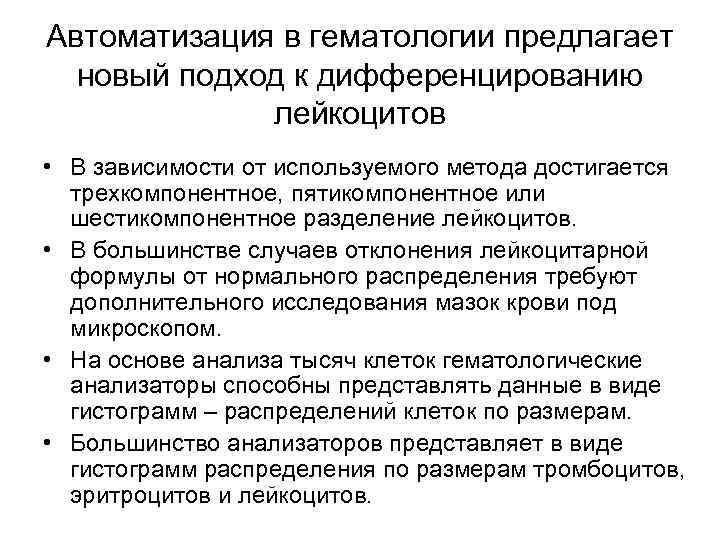

Автоматизация в гематологии предлагает новый подход к дифференцированию лейкоцитов • В зависимости от используемого метода достигается трехкомпонентное, пятикомпонентное или шестикомпонентное разделение лейкоцитов. • В большинстве случаев отклонения лейкоцитарной формулы от нормального распределения требуют дополнительного исследования мазок крови под микроскопом. • На основе анализа тысяч клеток гематологические анализаторы способны представлять данные в виде гистограмм – распределений клеток по размерам. • Большинство анализаторов представляет в виде гистограмм распределения по размерам тромбоцитов, эритроцитов и лейкоцитов.

Автоматизация в гематологии предлагает новый подход к дифференцированию лейкоцитов • В зависимости от используемого метода достигается трехкомпонентное, пятикомпонентное или шестикомпонентное разделение лейкоцитов. • В большинстве случаев отклонения лейкоцитарной формулы от нормального распределения требуют дополнительного исследования мазок крови под микроскопом. • На основе анализа тысяч клеток гематологические анализаторы способны представлять данные в виде гистограмм – распределений клеток по размерам. • Большинство анализаторов представляет в виде гистограмм распределения по размерам тромбоцитов, эритроцитов и лейкоцитов.